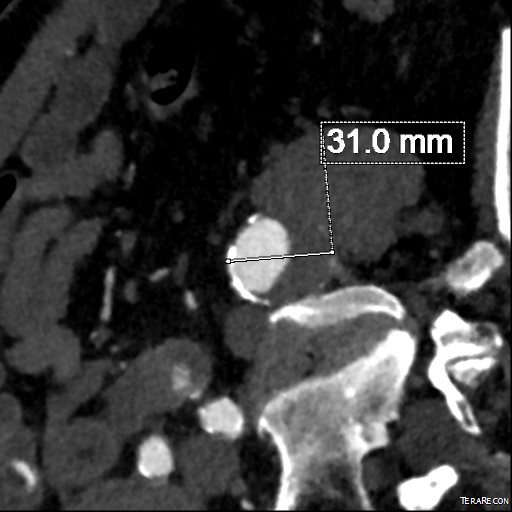

For example, take this patient who after EVAR of aortic aneurysm with AFX developed metachronous dilatation of the common iliac artery to 3.9cm with abdominal pain. The average diameter is 18.5mm. From the table, that rounds to 19mm corresponding to 283.53 square mm. If the internal iliac artery requires a 13mm graft, that is 132.73 square mm, the difference being 150.80 square mm. That corresponds to a 14mm diameter graft, but a slightly larger graft is preferred for oversizing. The external iliac artery is 8mm, and putting a 13mm Viabahn (largest available) in that would result in the B-infolding in the 8mm external iliac. Here, I bailed myself out by simply placing a 20mm AFX iliac limb extension, which by virtue of its design is resistent to infolding and tolerant of parallel grafts laid alongside in constricted channels. I found that the AFX iliac limb, a 20-13mm x 88mm length extension well suited for this.